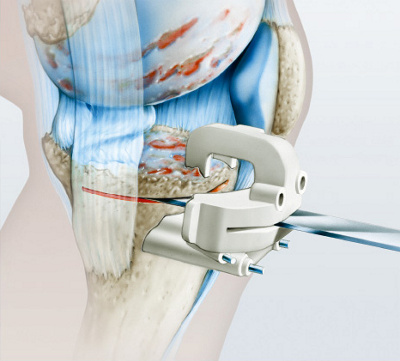

kniegelenkprothese_roentgenbild

Abb. 2

Röntgenbild mit einseitig völlig ­verbrauchtem Knorpel. Die Knochen ­schleifen aufeinander.